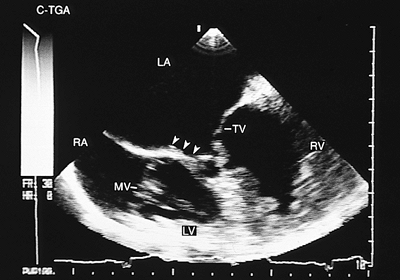

Congenitally Corrected Transposition

In congenitally corrected transposition, both the A–V and the V–A connections are discordant. Associated defects, especially ventricular septal defect, either isolated or with pulmonary valve stenosis, are common, occurring in 70% to 90% of cases. Cardiac malpositions also are commonly associated and can make it difficult to obtain satisfactory transthoracic recordings. The study of these patients should include transesophageal and transgastric recordings, and the main findings are discussed in the following paragraphs (4).

A–V discordance is established by identifying atrial situs and the position of the ventricles using the criteria discussed at the beginning of the chapter. The most reliable way of identifying the atria is through the morphology of the atrial appendages. The principal signs used for the identification of the ventricles are the different levels of implantation of the mitral and tricuspid septal leaflets (when ventricular septal defect is absent) and insertion of the tricuspid chordae tendineae in the interventricular septum. In addition, the ventricular morphology evident in the four-chamber image facilitates recognition—the right ventricular chamber has a triangular shape and the left ventricular chamber an ellipsoid form. These characteristics are independent of the ventricular spatial relationship.

In V–A discordance, identification of the great arteries is based on the bifurcation of the pulmonary artery. The parallel positions of the two vessels can be observed with monoplanar recordings taken at the level of the semilunar valves. When situs is solitus, the aorta is anterior and to the left and the main pulmonary artery posterior and to the right (Fig. 8.2.48). In situs inversus the aorta is anterior but to the right of the main pulmonary artery.

Abnormalities of the A–V valves are not uncommon; the tricuspid valvular anomaly known as left-sided Ebstein anomaly is noteworthy. In patients with this anomaly, it is possible to recognize tethering of the septal leaflet to the interventricular septum in the transesophageal four-chamber image and to evaluate the severity of valvular regurgitation with color Doppler (Figs. 8.2.49 and 8.2.50).

FIGURE 8.2.49. Left-sided Ebstein anomaly. Four-chamber image in a patient with corrected transposition of the great arteries (C-TGA). Tethering of the tricuspid septal leaflet to the ventricular septum is present (arrows). The anterior tricuspid leaflet (TV) shows ample movement. LA, left atrium; LV, left ventricle; MV, mitral valve; RA, right atrium; RV, right ventricle.